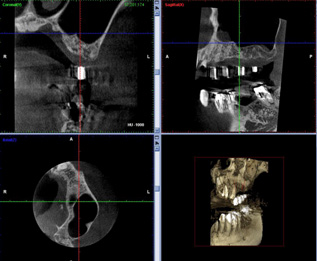

当院では、インプラントのオペの前にステントを装着しCTによる顎の骨の分析を行います。 |

この状態でインプラントを埋入すると隣の自分の歯と接蝕してしまうこと、また骨が不足しているので骨造成が必要なことがわかりました。修正が必要です。

撮影用ステントにより得られた情報を基に修正してサージカルステントにします。サージカルステントとはX線撮影用ステントとおなじく主に透明樹脂でできたマウスピースのような型でインプラントのオペの際にインプラントを埋め込む位置を確認するために使います。